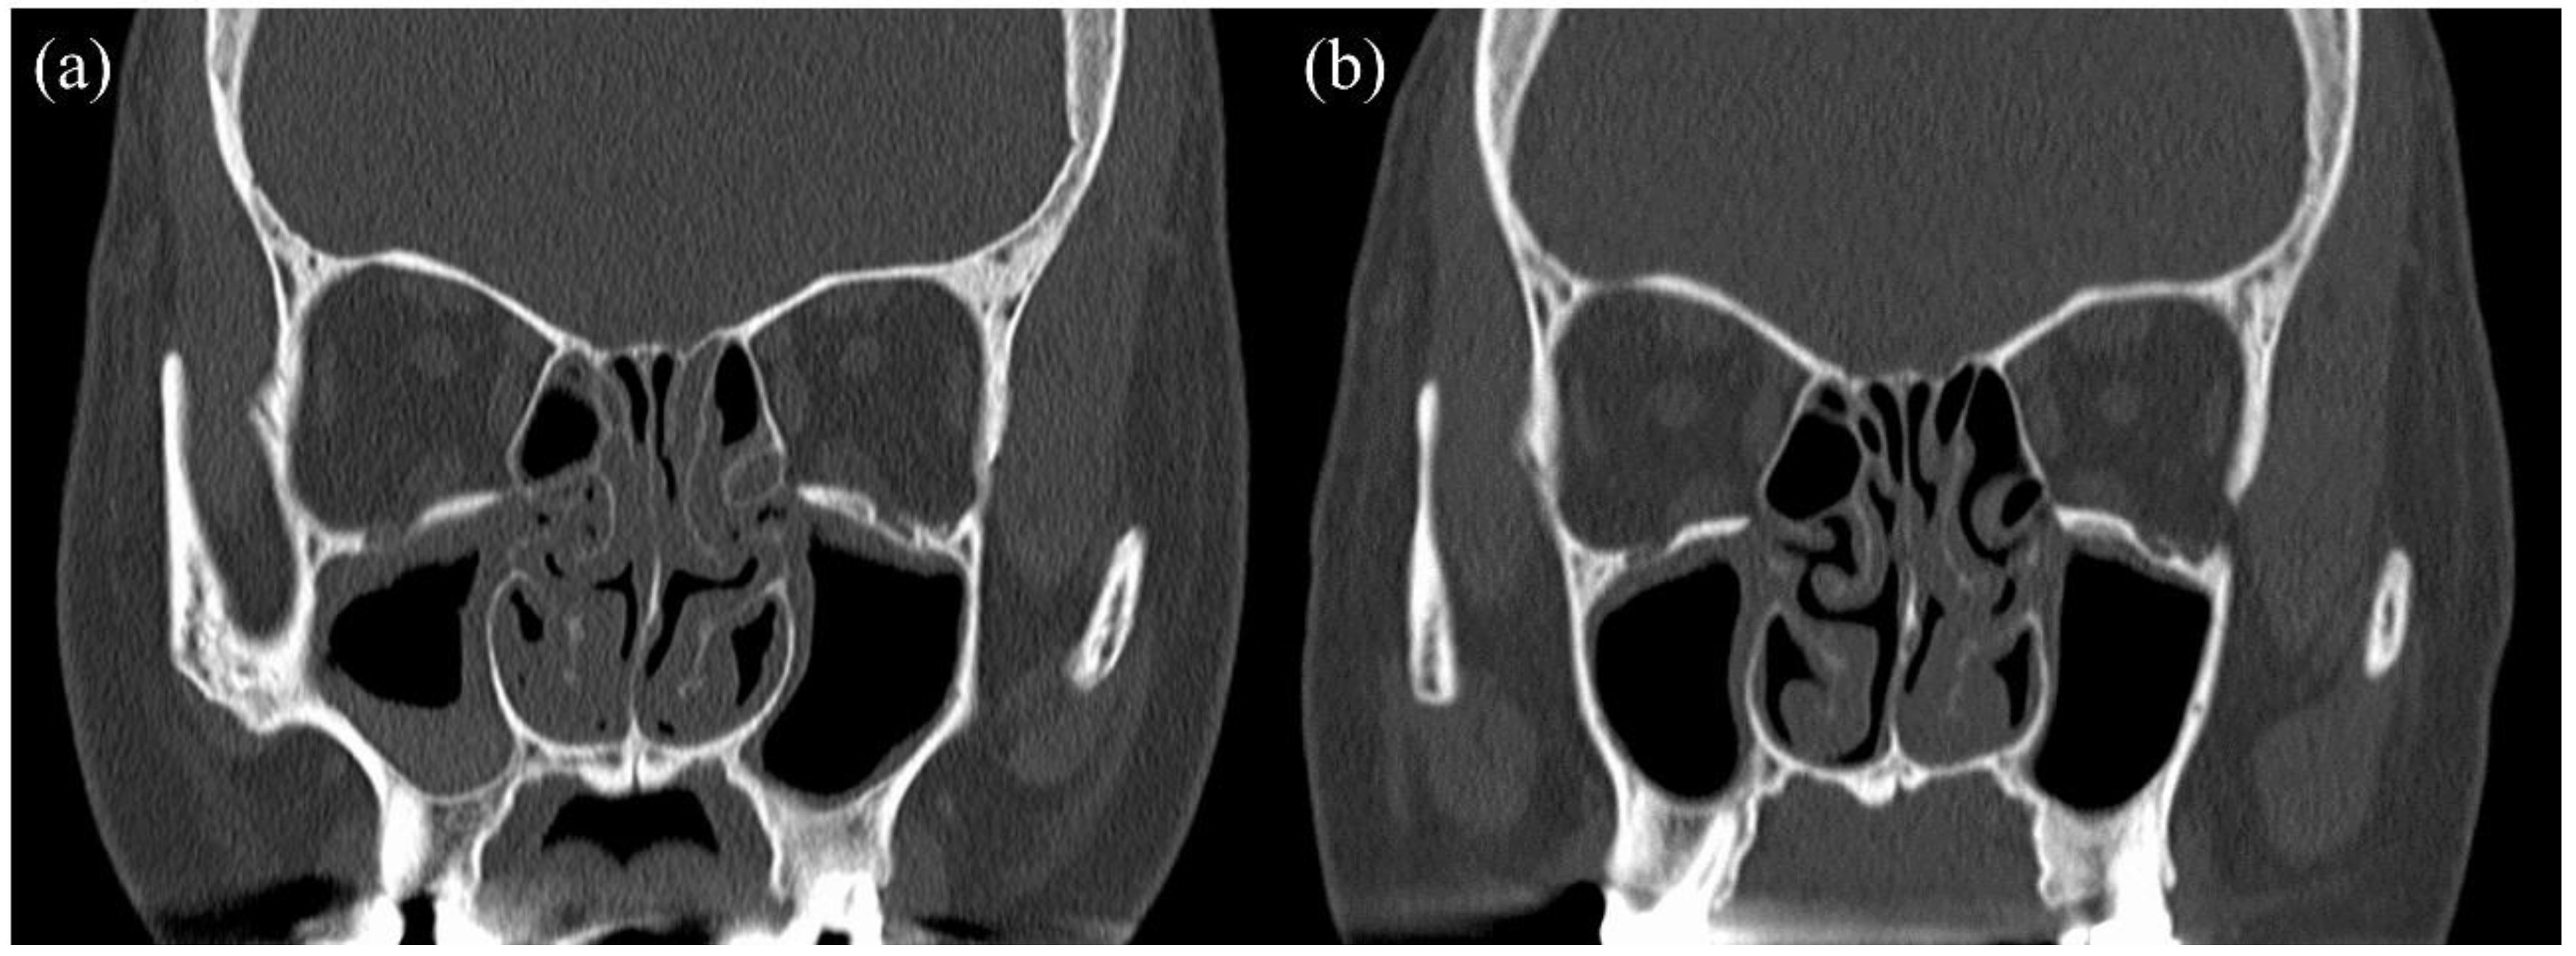

2. Case Report